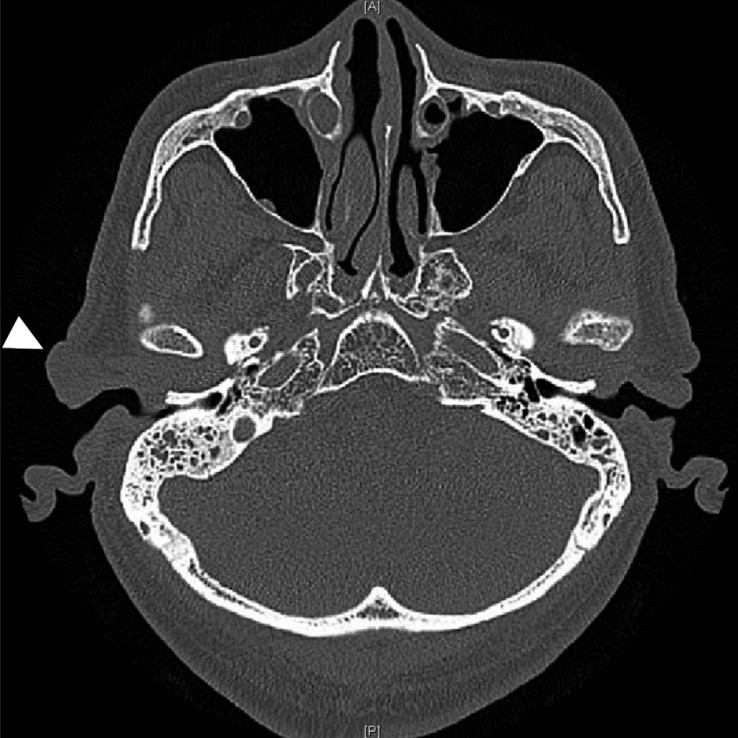

Isolated myxomas of the external auditory canal are extremely rare, benign tumors. We present a case of a 77-year-old male patient who presented with a benign mass in the right external auditory canal. Isolated myxomas of the tragus around the external auditory canal are rare. This case report highlights the clinical presentation, surgical management, and pathological findings of this patient. The importance of considering myxoma in the differential diagnosis of benign tumors of the external auditory canal is emphasized. Long-term follow-up is necessary to monitor for potential recurrence or associated conditions. Further studies are needed to better understand the etiology, pathogenesis, and optimal management of this rare type of tumor.